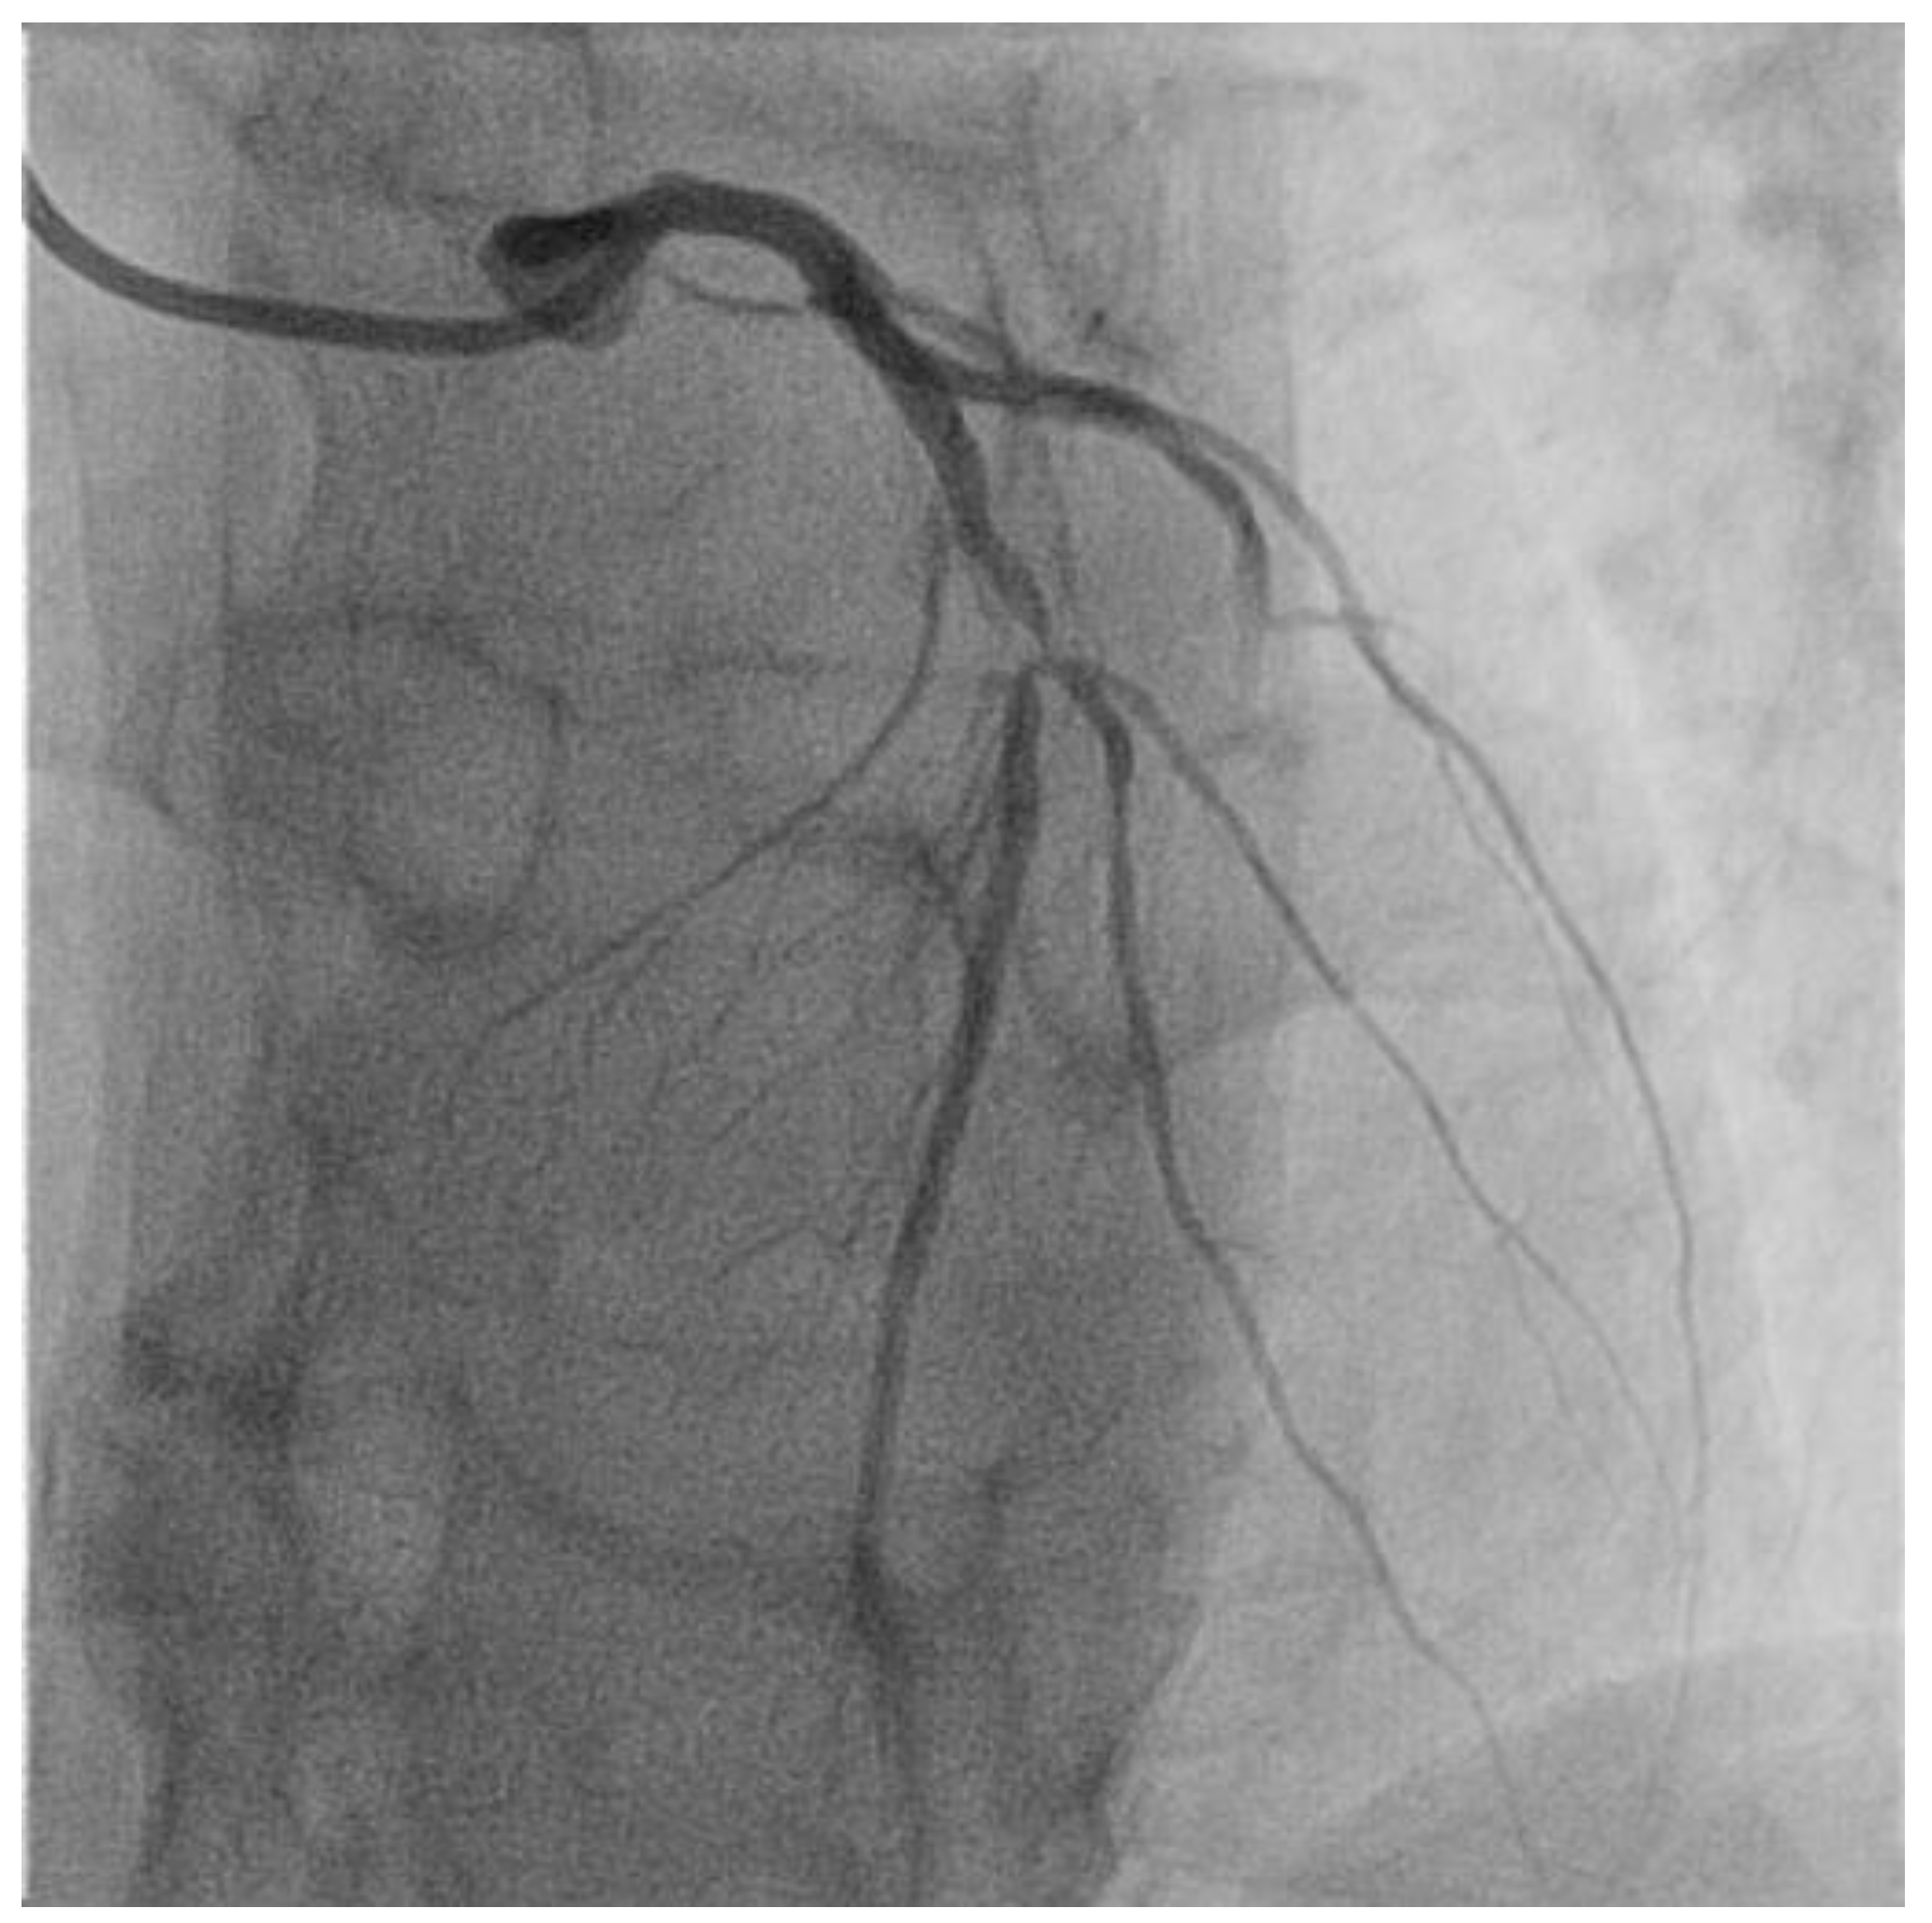

- Choi, B.-J.; Prasad, A.; Gulati, R.; Best, P.J.; Lennon, R.J.; Barsness, G.W.; Lerman, L.O.; Lerman, A. Coronary endothelial dysfunction in patients with early coronary artery disease is associated with the increase in intravascular lipid core plaque. Eur. Heart J. 2013, 34, 2047–2054. [Google Scholar] [CrossRef]